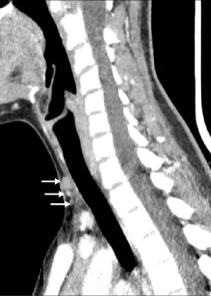

В то же время, во время сцинтиграфии паращитовидных желез с 99мТс-МИБИ не было отмечено накопления препарата. Далее была проведена четырехмерная компьютерная томография (4D КТ), которая не показала наличия глубоких узлов в средостении (рис. 8-11)). По результатам обследования был исключен синдром множественной эндокринной неоплазии (МЭН), хотя семья отказалась от генетического тестирования.

Рисунки 8-11. Снимки 4D КТ в поперечной (8,9), сагиттальной (10) и коронарной (11) плоскостях, где заметны слегка контрастируемые узелки в претрахеальной подкожной клетчатке (8-10) и в нижнем полюсе левой доли щитовидной железы (11). Размеры варьируют от 3 до 12 мм.